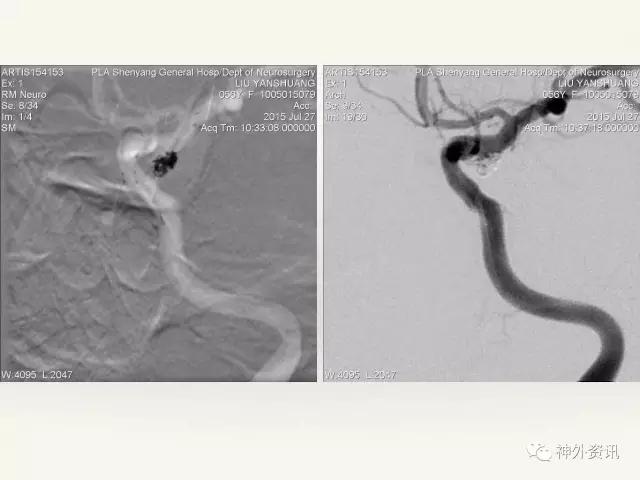

在东北地区率先开展了颈内动脉、大脑中动脉及基底动脉闭塞血管内再通、颅内动脉栓塞急性期取栓、血流导向装置治疗大型宽颈动脉瘤等,对颅内动脉瘤、动静脉畸形、颈动脉及颅内动脉狭窄、颈内动脉海绵窦瘘、硬脑膜动静脉瘘等外科治疗具有较深的造诣。完成脑血管造影8600余例,各类脑血管病介入手术共4500余例,动脉瘤、动静脉畸形、脑肿瘤、脑出血及脑外伤等外科手术1500余例。